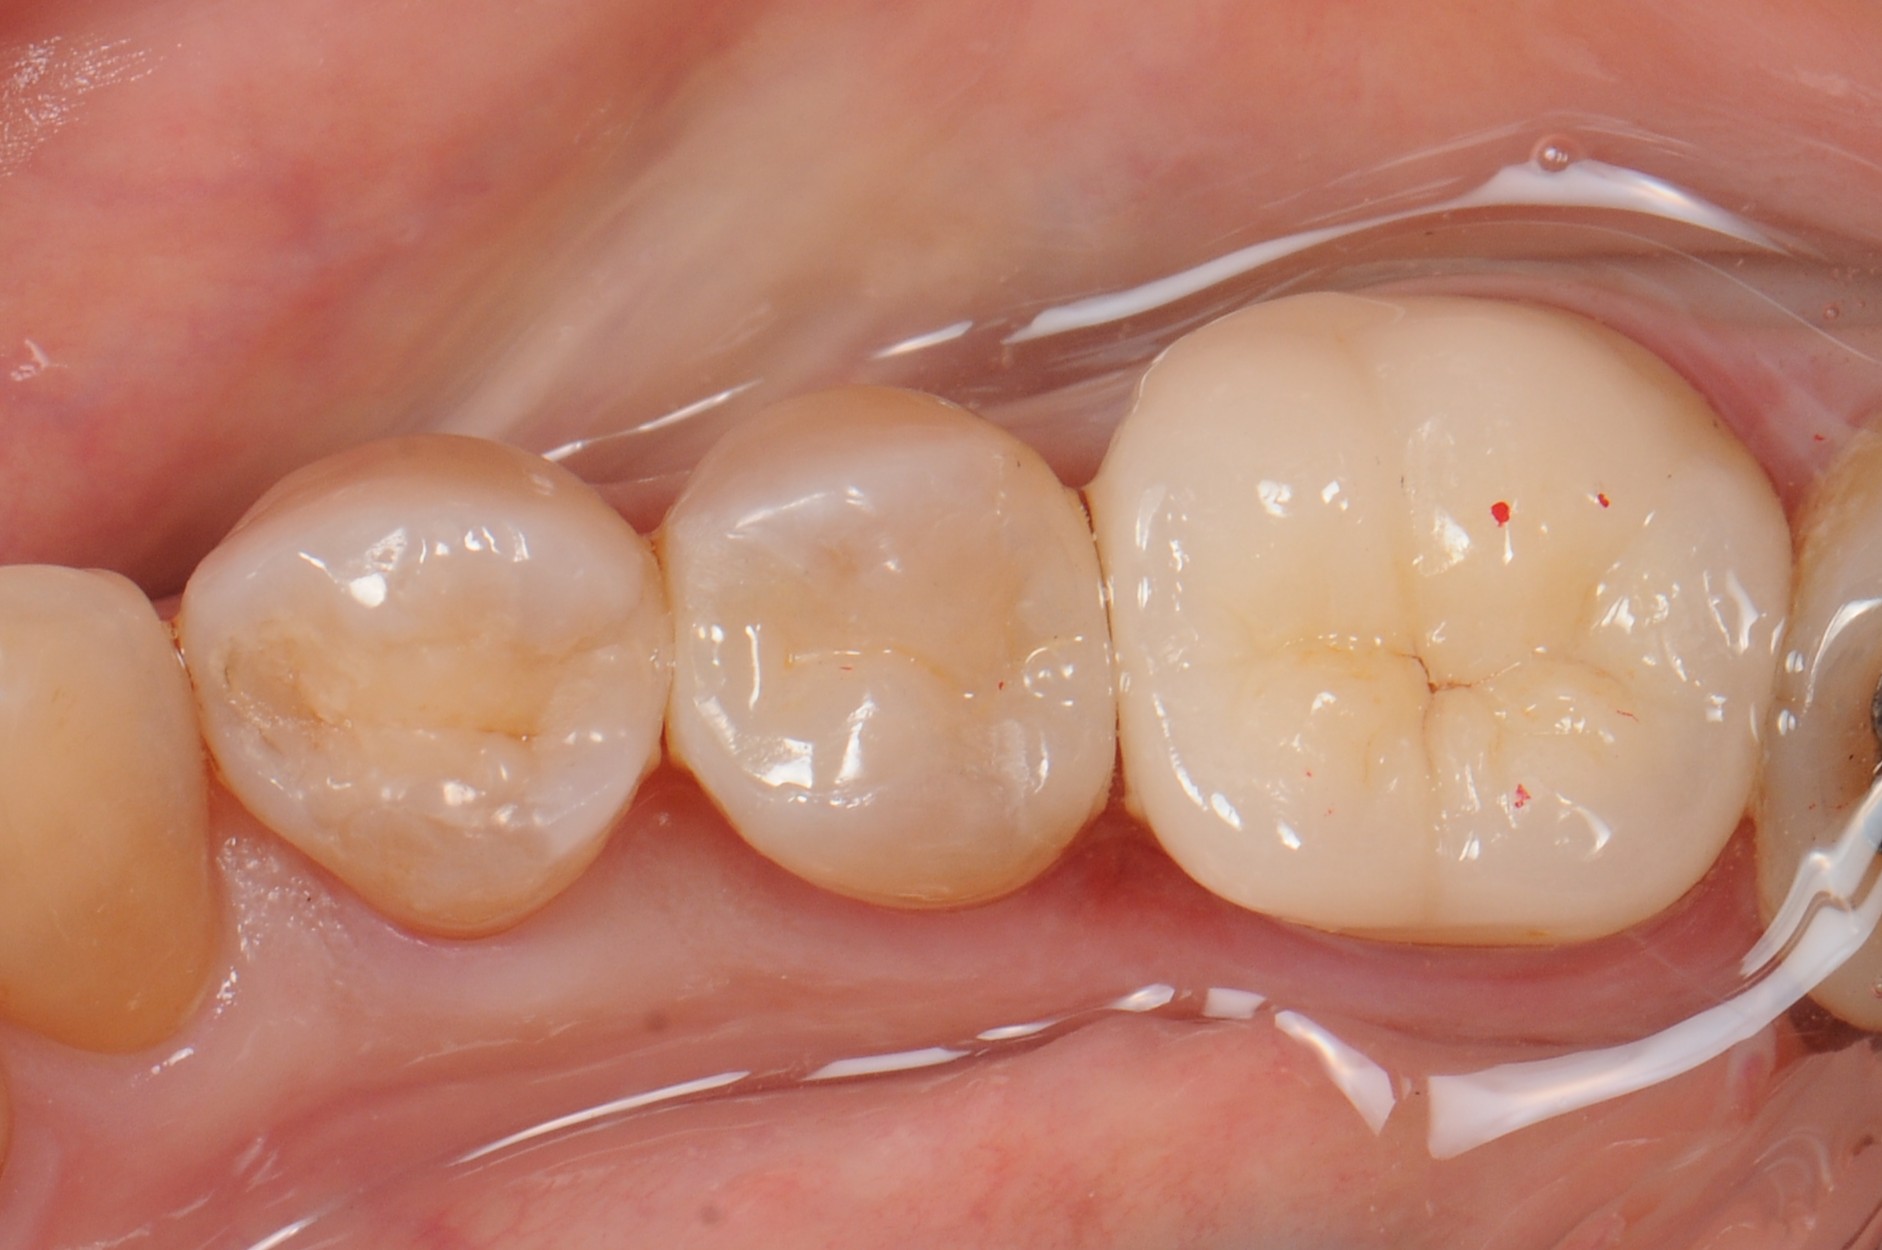

case8 症例(セラミックインレー・ダイレクトボンディング)

治療前

治療後

| 費用(税込み) | セラミックインレー:66,000円、ダイレクトボンディング:22,000円 |

|---|---|

| 治療回数 | 1歯につき3回 |

| 主訴 | 金属の修復物を白くししたい |